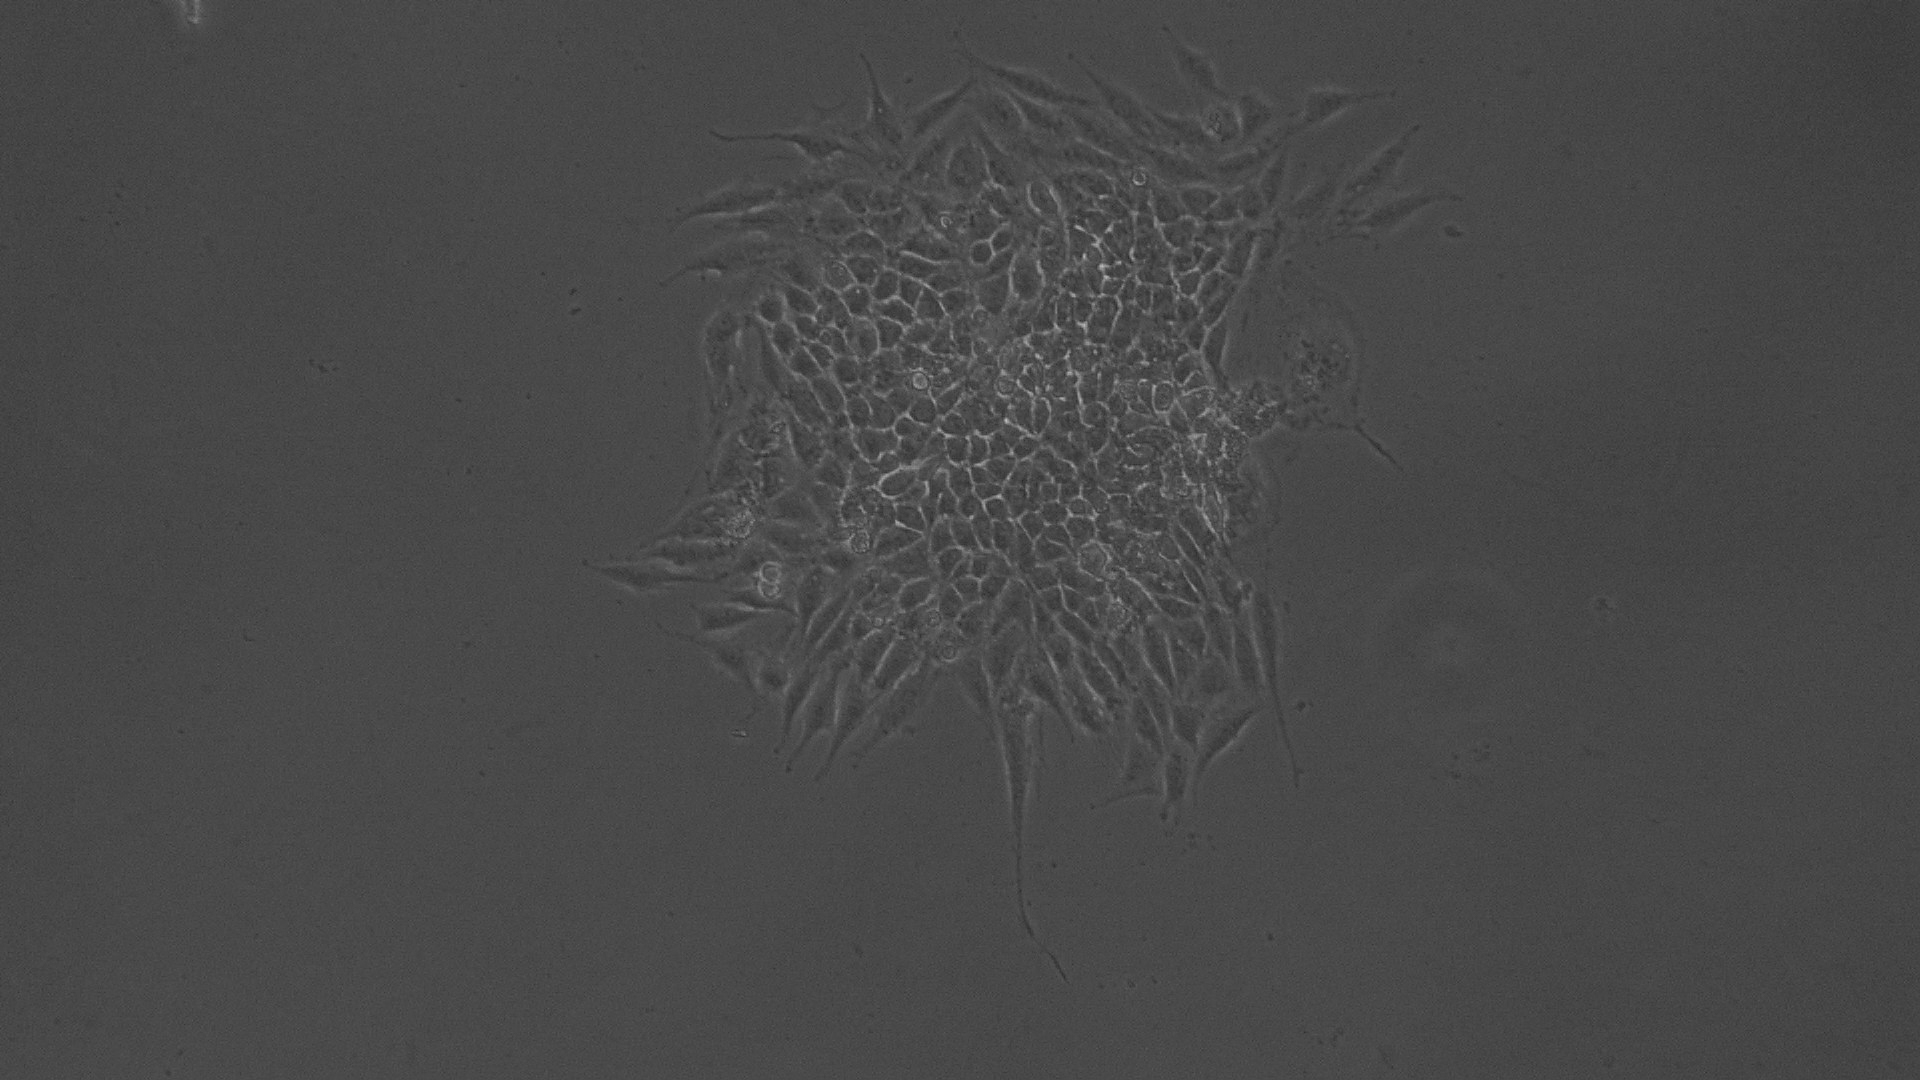

Antiproliferative effect by direct microscopic observation

The entire plate was observed at an interval of every 24 h; up to 72 h in an inverted phase-contrast tissue culture microscope (Labomed TCM-400 with MICAPSTM HD camera) and microscopic observations were recorded as images. Any detectable change in the morphology of the cells, such as rounding or shrinking of cells, granulation, and vacuolization in the cytoplasm of the cells, were considered as indicators of cytotoxicity.

Fig. 5: Morphological changes showing inhibition of Hela cell lines by different concentrations of ethanolic extract of leaves of Pothos scandens. a: -ve control (95% ethanol), b: 6.25 µg/ml, c: 12.5 µg/ml, d: 25 µg/ml, e: 50 µg/ml f: 100 µg/ml

In vitro anti-cancer activity

In vitro anticancer actiivity of ethanolic extract of leaves of Pothos scandens Linn. was evaluated against HeLa and MCF 7 cell lines. The viability of cells was evaluated by direct observation of cells by an Inverted phase contrast microscope and MTT assay method. The morphological changes in HeLa and MCF 7 cells after treatment with the extract and standard doxorubicin are shown in fig. 5, 6, 7 and 8. The IC50 values are shown in table 4.

According to the American National Cancer Institute (NCI), crude extracts with an IC50<30 μg/ml are considered to be active against cancer cells [32, 33]. Different concentrations of the ethanolic extract of leaves of Pothos scandens Linn. exhibited potent cytotoxic activity against HeLa and MCF 7 cell lines with IC50 of 22.9 and 18.32 μg/ml, respectively.